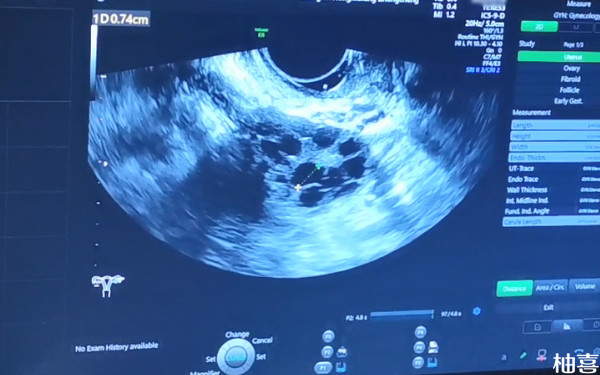

打促排卵的针以后卵泡只长了三个建议取卵吗?

打促排卵的针以后卵泡只长了三个,并且都发育成熟的话,还是可以进行取卵的,毕竟只要是已经发育成熟的卵子都具有一定受精能力,如果受精成功并发育成为三天卵裂期胚胎或者是5-6天的囊胚即可在医务工作人员的指导下进行移植,这样妊娠率可能会更高一些,但具体是否能怀孕成功,还需要考虑到自身实际情况。